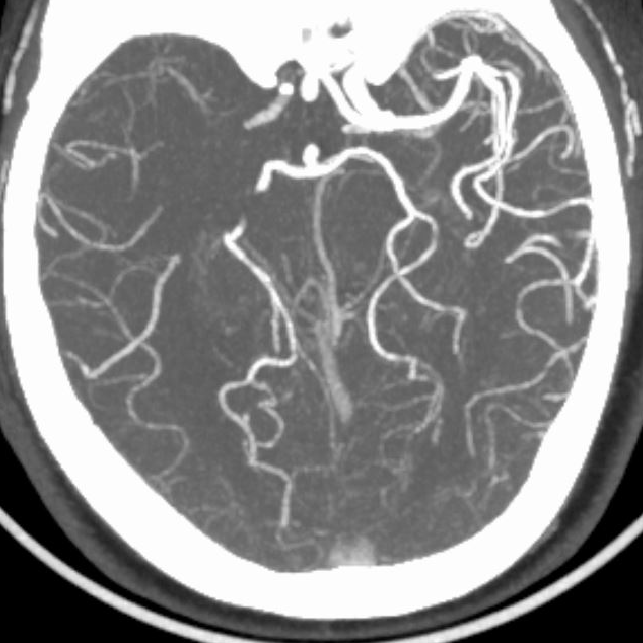

术前CTA:

CTA提示右侧大脑中动脉闭塞,左侧A1纤细。

延迟CTA扫描可见造影剂逆流至大脑中动脉主干。